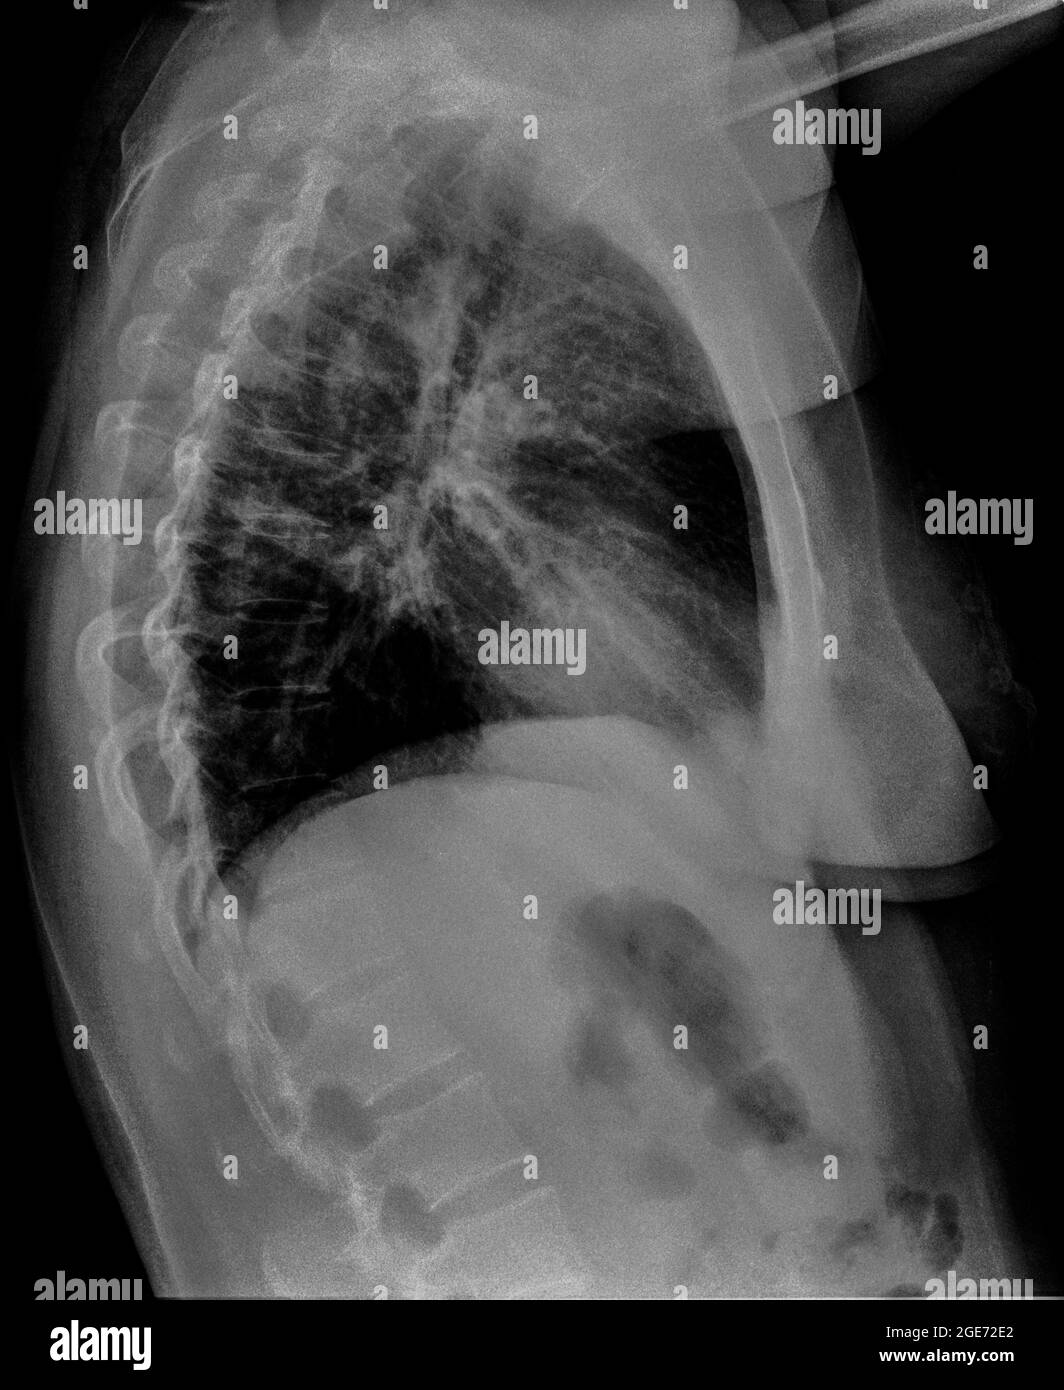

From www.alamy.com

Chest anatomy hires stock photography and images Alamy Chest X Ray For Pneumonia Views If pneumonia is suspected, your doctor may recommend the following tests: The diagnosis of cap generally requires the demonstration of an opacity on chest imaging in a patient with a clinically compatible. The many faces of pneumonia. Plain chest radiography is an inexpensive test that can rapidly demonstrate the presence of pulmonary abnormalities. It represents an important initial examination in. Chest X Ray For Pneumonia Views.